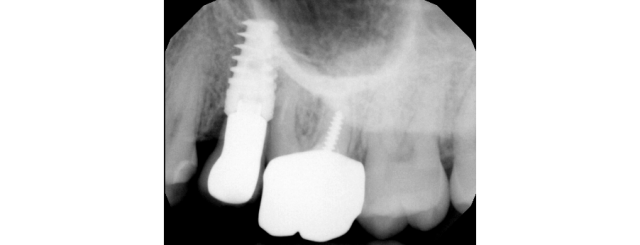

• What doesn’t she like? Are there open contacts? Lack of papilla? I’m more concerned about MB root proximity. I am not sure if a new crown will fix the underlying lack of bone between the implant and root. I feel that this can only be fixed with a root amputation, graft and sleeping the implant.